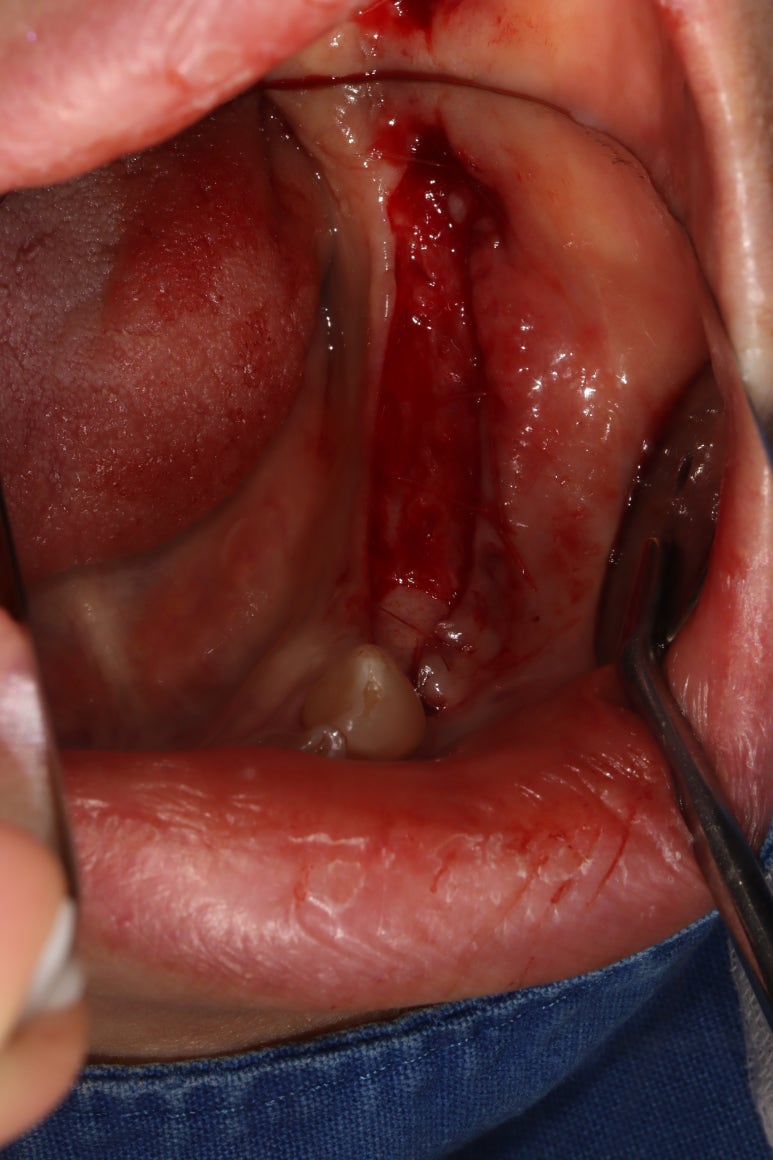

임플란트 2차수술 (3달 경과 후)

- 유리치은이식술 (free ginigval graft)

임플란트 1차수술을 마치고 정확이 3개월 뒤에 임플란트 2차수술을 시행하였습니다.

임플란트 2차수술을 하는 바로 이 시기가 유리치은이식술 (FGG)을 하기에 가장 좋은 시기입니다.

먼저 부분층 판막 (partial thickness flap)을 예쁘게 형성하여,

골막이 드러나는 환경을 만들어 줍니다.

원하는 크기를 선택하여 치유지대주를 연결해 줍니다.

부분층 판막을 형성하였기 때문에, 사실 가만히 두면 부착치은이 되어 회복될 것입니다만

어떤 퀄리티로 치유가 완성될지 모르는 불명확한 상황이므로 유리치은이식술이 최고입니다.